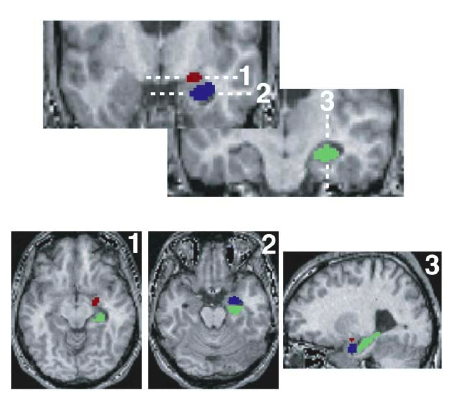

Etkin A, Klemenhagen KC,

Dudman JT, Rogan MT, Hen R, Kandel ER, Hirsch J

Individual Differences in Trait Anxiety Predict the Response of the Basolateral

Amygdala to Unconsciously Processed Fearful Faces

Cell 119(5):719-32